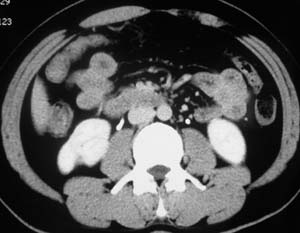

以下是引用子期在2010-3-19 20:47:00的发言:[br]血管畸形的ct增强应该有明显强化,本例并不相符合。本例双肾局部的略低密度影,累及肾盂,局部皮质明显变薄、内陷,增强扫描有轻度的强化,应考虑为炎性病变,患者为年轻男性,累及双肾的感染以结核较常见,可以没有明显的临床症状,尿中有时候也并不能查出什么;肾脓肿常有明显感染中毒症状,本例不符,另外一般的肾盂肾炎或肾小球肾炎通过小便就可确诊,其它还不能排除的是黄色肉芽肿性肾盂肾炎,然而单凭ct一般也很难鉴别。